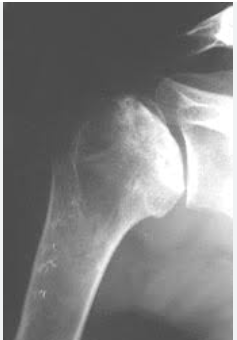

Qual origem, inervação e inserção do músculo assinalado?

Origem: clavícula, acrônimo e espinha da escapula Inserção: tuberosidade do deltoide e úmero Inervação: nervo axilar (c5-c6)